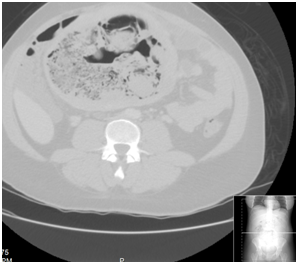

Patients Chest X-ray revealed normal findings. Pelvic ultrasound (Figure 1) showed enlarged uterus 16.9 cm x 10.59 cm x 4.95 cm with heterogeneity compatible with a history of multiple large leiomyomas. There were multiple dirty shadows with ring down densities suggestive of air within the uterine parenchyma. A loculus of fluid within the uterus was also noted (Figure 1). Abdominal CT imaging (Figure 2) (Figure 3) confirmed an enlarged lobular uterus. There were heterogenous multilobular masses with decreased attenuation and numerous foci of internal gas. Findings were most consistent with a necrotic fibroid, lesion measured 20 x 11.4cm. Gas was present within the lesion anteriorly and findings consistent with fluid rather than soft tissue density seen within the adjacent portions of the lesion (Figure 2) (Figure 3). No free intraperitoneal air was noted. Patient was soon after admitted to the Gynecology service with a diagnosis of Pyomyoma.

Figure 2 Patient Number 1, Computerized Tomography of Abdomen and Pelvis, Axial View: enlarged heterogenous multilobular masses within uterus, measuring 20 x 11.4 cm, consistent with Infarcted fibroid after embolization with internal gas, air and debris as expected after uterine artery embolization (UAE).